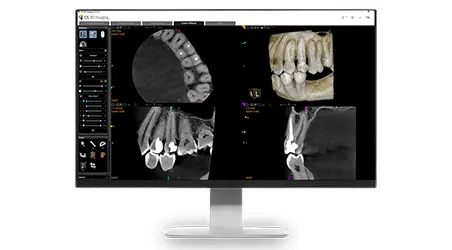

Enhanced Diagnostics

Capture detailed 3D images of teeth, bone, nerves, and soft tissue—seeing what traditional X-rays often miss. Perfect for identifying complex issues early.

Personalized Treatment Planning

Each scan provides precise data for implants, root canals, TMJ therapy, or orthodontics, ensuring accuracy and comfort from day one.